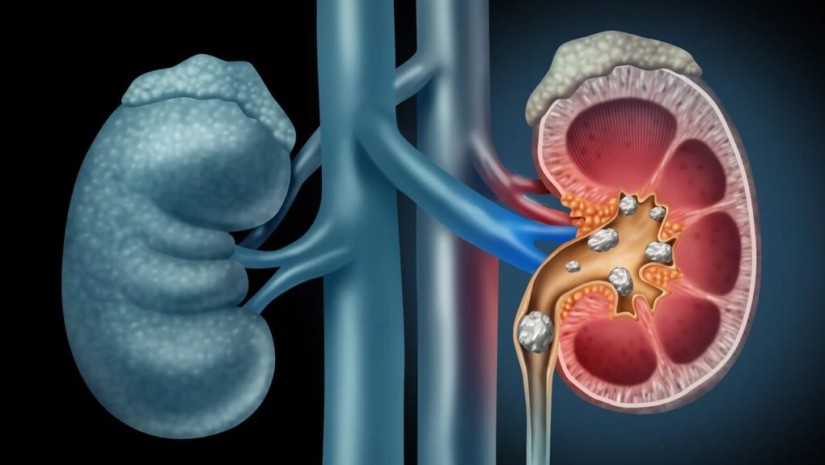

პირველად ისტორიაში, მეცნიერებმა აღმოაჩინეს, რომ თირკმლის კენჭებში ბაქტერიები იმალება. პატარა კრისტალების ეს გაქვავებული კენჭები შედგება შარდში არსებული ქიმიური ნივთიერებებისგან და მიჩნეულია, რომ წარმოიქმნება სითხის ნაკლებობით ან მინერალებისა და ქიმიურ ნივთიერებათა მაღალი კონცენტრაციით.

ლოს-ანჯელესის კალიფორნიის უნივერსიტეტის (UCLA) მკვლევრებმა აღმოაჩინეს, რომ კალციუმის ოქსალატის თირკმლის კენჭები (ყველაზე გავრცელებული ტიპი) გამდიდრებულია ბაქტერიებით.

უფრო მეტიც, შინაგან სტრუქტურის სახით, ეს კენჭები ბაქტერიების ფენებს შეიცავს.

ელექტრონული და ფლუორესცენტული მიკროსკოპის გამოყენებით, პაციენტისგან აღებულ კალციუმის ოქსალატის კენჭებში მკვლევრებმა აღმოაჩინეს ბაქტერიების სტრუქტურული და ქიმიური მტკიცებულება.

თირკმლის კენჭები ცხოვრების განმავლობაში, ყოველი 11 ადამიანიდან ერთს უჩნდება; შემთხვევათა 70 პროცენტი კი დაკავშირებულია კალციუმის ოქსალატის ქვებთან.